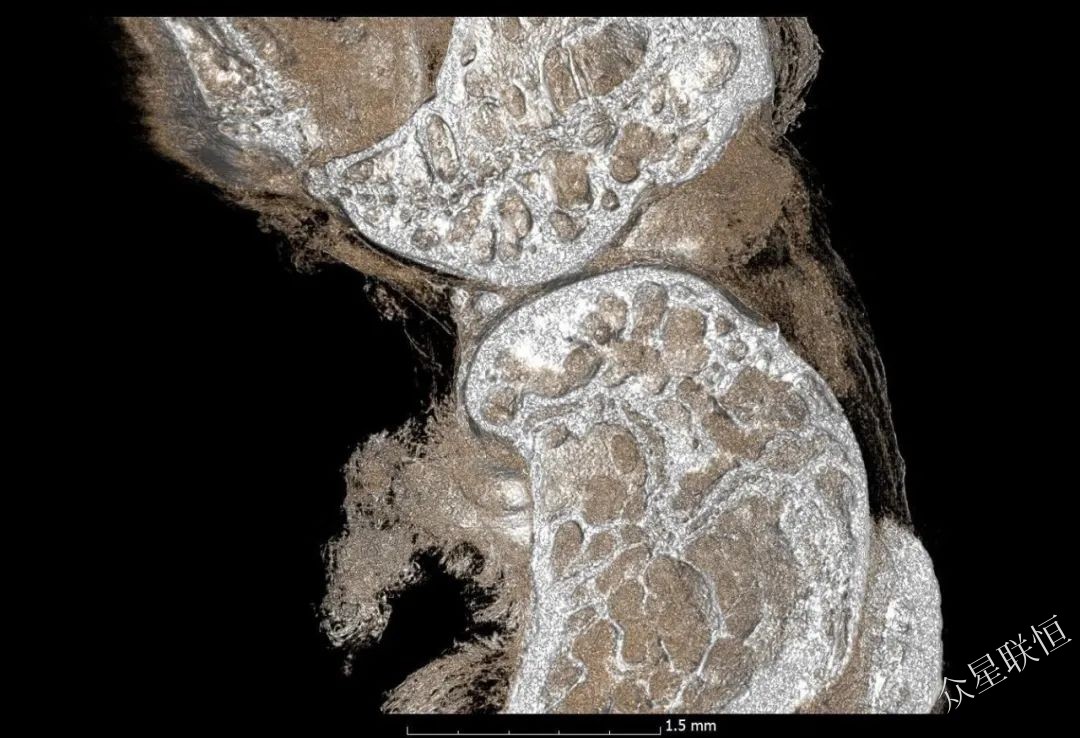

下圖展示了相襯可以更好地顯示甜椒種子細(xì)節(jié)特征

不含相襯信息

含相襯信息

鈦植入樣品

圖像顯示了整形外科的鈦植入物,可用于不同的應(yīng)用,即檢查骨-植入物的界面。 注意,相襯改善了骨骼結(jié)構(gòu)的可視化。